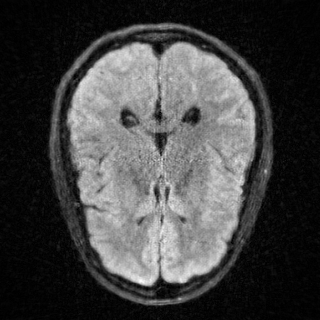

This article presents a novel undersampled magnetic resonance imaging (MRI) technique that leverages the concept of Neural Radiance Field (NeRF). With radial undersampling, the corresponding imaging problem can be reformulated into an image modeling task from sparse-view rendered data; therefore, a high dimensional MR image is obtainable from undersampled $k$-space data by taking advantage of implicit neural representation. A multi-layer perceptron, which is designed to output an image intensity from a spatial coordinate, learns the MR physics-driven rendering relation between given measurement data and desired image. Effective undersampling strategies for high-quality neural representation are investigated. The proposed method serves two benefits: (i) The learning is based fully on single undersampled $k$-space data, not a bunch of measured data and target image sets. It can be used potentially for diagnostic MR imaging, such as fetal MRI, where data acquisition is relatively rare or limited against diversity of clinical images while undersampled reconstruction is highly demanded. (ii) A reconstructed MR image is a scan-specific representation highly adaptive to the given $k$-space measurement. Numerous experiments validate the feasibility and capability of the proposed approach.